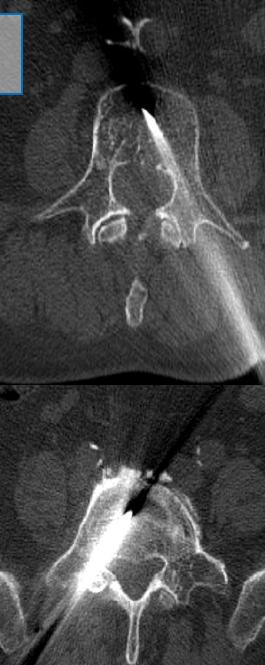

The procedure is performed under conscious sedation (local anesthesia with intravenous analgesia and mild sedation) or, in selected cases, general anesthesia.-

Percutaneous access through the pedicle under CT or fluoroscopic guidance

-

Precise needle positioning within the vertebral body

- Controlled injection of bone cement with real-time monitoring